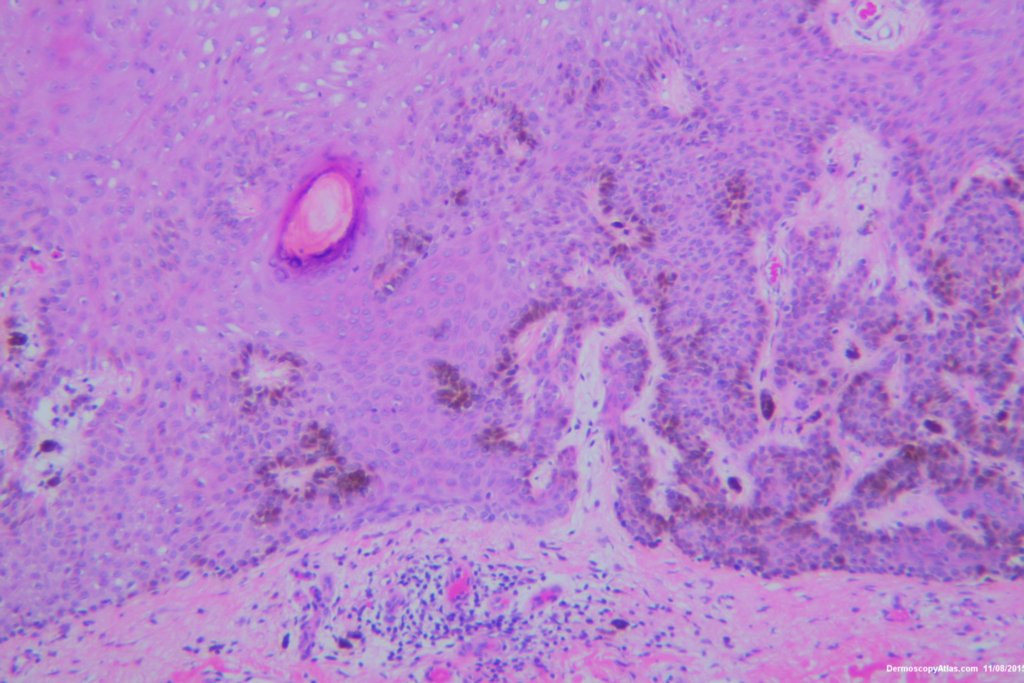

Diagnosis: Seborrhoeic keratosis irritated

This lesion looked darker than the many other seborrhoeic keratoses on this elderly man's back. It was thought there might be a lentiginous proliferation of atypical melanocytes in the lesion . Also the multiple colours and the white lines were unusual for a seborrhoeic keratosis. However pathology of a large shave biopsy excision showed only a pigmented thick seborrhoeic keratosis with increased pigment in normal basal keratinocytes. The blue colour was because of the depth of the lesion ie thick. No idea why the white lines!